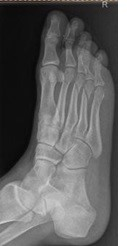

Na rentgenogramie stopy uwidocznione jest złamanie

A. I i V kości śródstopia.

B. paliczka bliższego palca I i II.

C. III i IV kości śródstopia.

D. paliczka bliższego palca I i V.